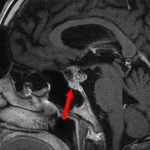

No.’25_60 手術前1

No.’25_60 手術前2